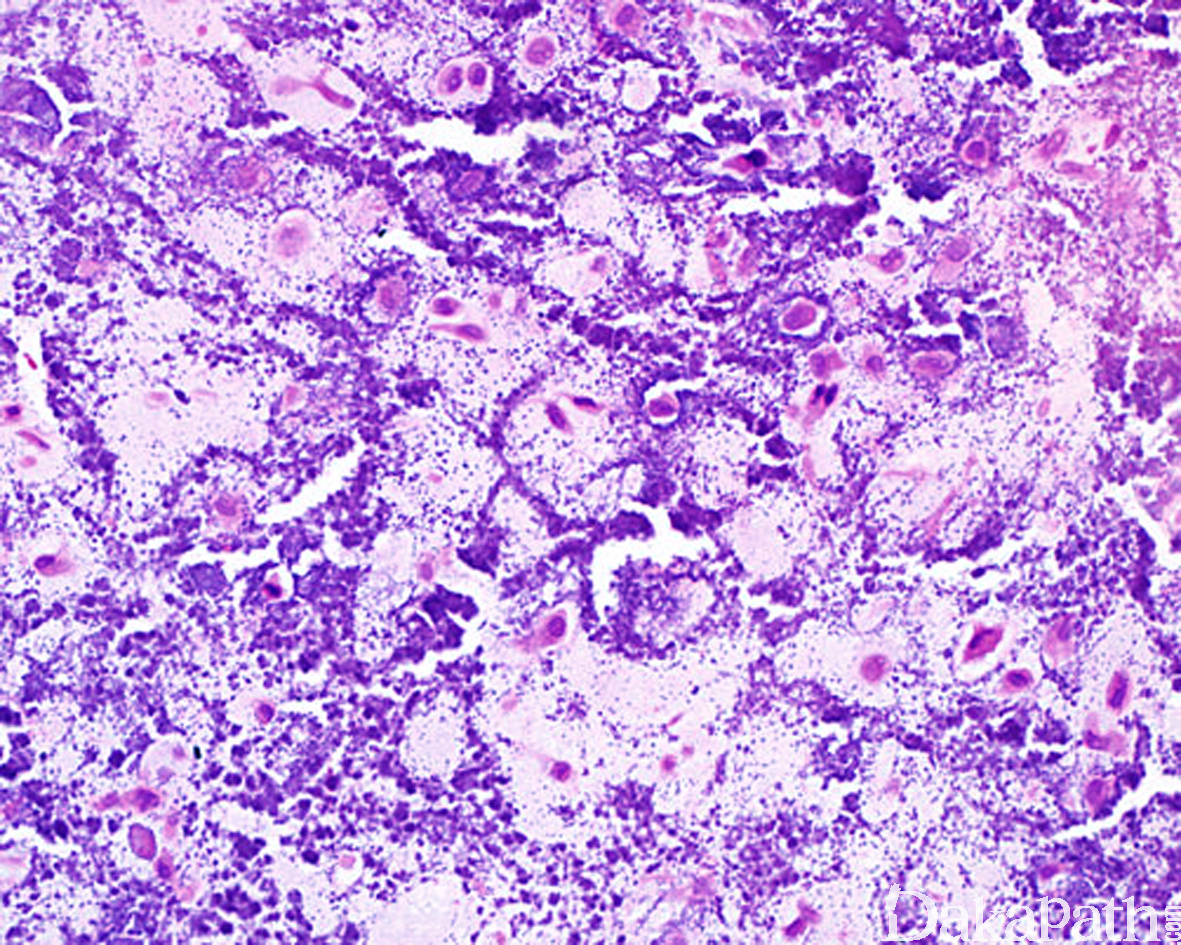

低倍镜下大多数病例由排列成分叶状的成熟性透明软骨组成,部分病例可伴有纤维化、钙化、骨化或黏液样变性,有时候钙化非常明显使得基础的软骨病变难以察觉。与正常的透明软骨相比,软组织软骨瘤的瘤细胞相对较丰富,可类似于 I 级软骨肉瘤的细胞学特征,无细胞的非典型性,无增多的核分裂象;

一些病例内软骨细胞相对较为丰富,且细胞体积较大,可见核沟或核裂,含有多少不等的软骨样基质,常见围绕软骨细胞的钙化,肿瘤内常可见散在分布的破骨样巨细胞,形态上类似软骨母细胞瘤,也称软骨母细胞瘤样软骨瘤(chondroblastoma-like chondroma)。